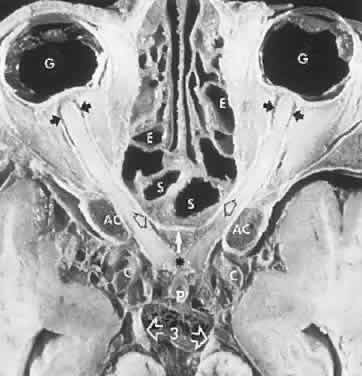

The retinal variety may be admixed in a person who suffers the more conventional attacks of migraine. It is presumed that vasospasm in the retinal circulation determines transient hypoxia, perhaps somewhat similar to the visual cortical event. On rare occasions, the fundus has been examined during typical retinal migraine episodes, and arterial constriction has been described. Wolter and Burchfield106 photographically documented such an episode and demonstrated mild “retinal edema”; vessel narrowing is also evident (Fig. 8). Fortunately, permanent complications of retinal migraine are rare. These may take the form of central retinal artery occlusion or ischemic papillopathy (see Volume 2, Chapter 16); nerve fiber bundle visual field defects may be demonstrated (Fig. 9).

Fig. 8. Retinal migraine. A. During amaurotic episode. Note the dusky appearance of the fundus, increased retinal sheen (possibly edema), and dark narrowed veins (arrows). The disc is also hyperemic. B. Fundus after episode. Compare paired arrows. (Courtesy of Dr. J. Reimer Wolter)